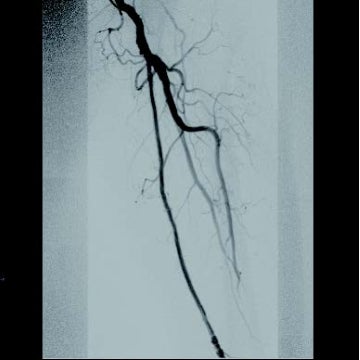

[背景] 左間欠性跛行で14年前に左SFAにベアナイチノールステント6 mm × 120 mm 2本が留置されている(図1)。約7年前に左間欠性跛行が増悪し、来院。外来での超音波検査でベアステントの完全閉塞を認めた(図2)。高度の跛行があり、再治療を実施した。